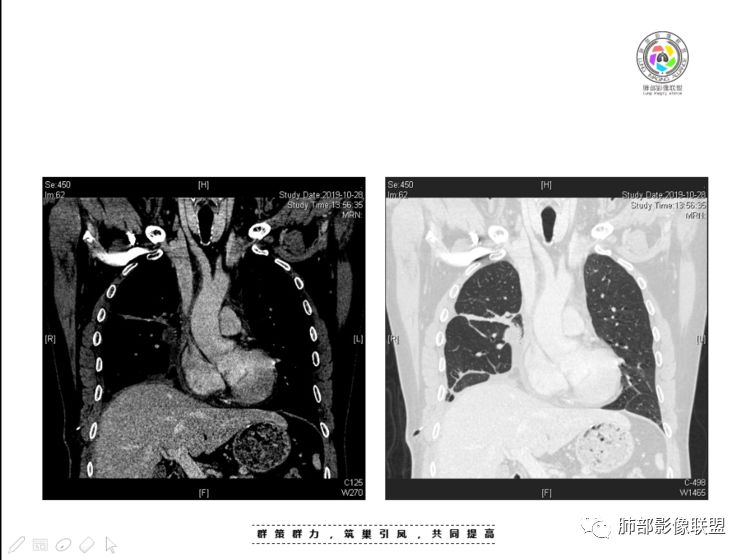

本例纵隔与肺内两处病变,回顾总结分析:

1、右肺内病灶,病灶呈结节样,边缘欠规则,局部膨隆,叶间裂胸膜牵拉凹陷,再看相应支气管腔堵塞截断,临床资料胸水中查到癌细胞,均提示病灶倾向恶性,腺癌的病理意见与之相吻合。

黄勇老师总结,腺癌如果与胸膜、叶间裂紧贴或伴胸膜凹陷,胸膜、叶间裂多发结节,应当高度怀疑腺癌转移。

2、前纵隔内病灶囊实性混杂密度病灶,囊性病灶主要位于右侧,张力较高,有分隔影,囊壁右侧缘光整,病灶左侧实性部分边界不清明显强化,病灶肺瘤交界面大部分边界清楚,部分模糊。

胸腺瘤/胸腺癌:病灶内那么大的囊,常规考虑B型以上胸腺瘤,囊内有分隔影,病灶周围脂肪间隙模糊,常规考虑侵袭性胸腺瘤或胸腺癌,若侵袭性胸腺瘤,常侵犯胸膜、心包,很少累及肺。胸腺癌易侵犯胸膜、肺并纵隔淋巴结及远处转移。但肺内腺癌形态更符合原发灶。胸膜及叶间裂转移则即可来自肺,也可来自胸腺癌。

尽管前纵隔病灶缺乏相关病理资料,但是小编还是认为肺内与纵隔病灶以二元论解释。只是肺内恶性病灶引发的胸膜改变可能会影响我们对纵隔病灶的判断。